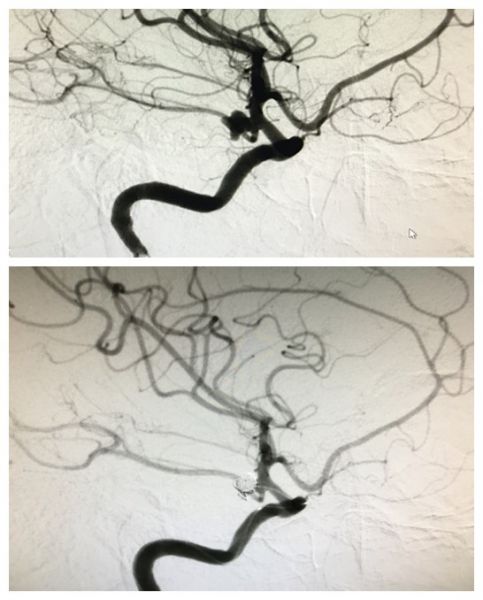

田先生,70岁,因突发剧烈头痛23小时入院。完善CTA提示:蛛网膜下腔出血,颅内双侧大脑中动脉M1段分叉部动脉瘤。神经外科二病区组织讨论后认为:患者颅内双侧大脑中动脉M1段分叉部动脉瘤,动脉瘤宽颈且巨大,行血管内介入治疗需要置入支架辅助,而患者家庭经济困难,治疗费用上无法承受;而开颅手术,患者为双侧动脉瘤,需要双侧开颅的话,手术创伤大,麻醉时间长,对病人机体打击大,手术风险极高,并发症明显。与患者家属多次积极沟通后,家属要求在我院行双侧大脑中动脉瘤开颅夹闭术。通过术前精心准备和研究手术预案,神经外科脑血管病团队决定采取单侧开颅行双侧大脑中动脉瘤夹闭治疗,这种手术方式减少了双侧开颅的创伤,减轻了患者的病痛,手术非常顺利。术后通过医护人员精心治疗和护理,患者恢复良好,未见明显并发症出现。据悉,单侧开颅行双侧大脑中动脉瘤夹闭治疗手术方式目前在省内属于领先地位,在国内能开展此类术式的医院也很少。